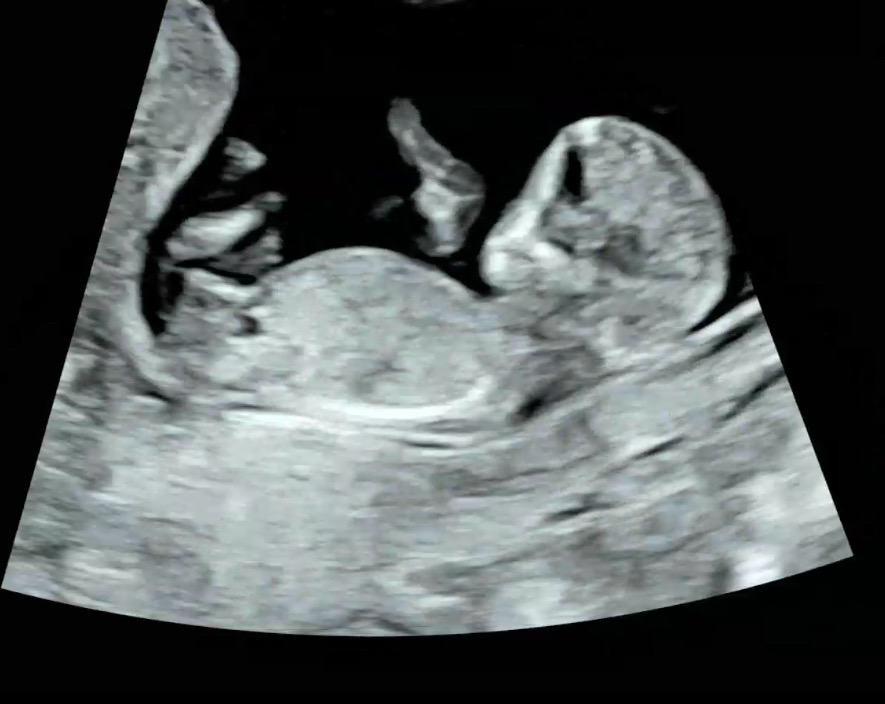

12주 1일차 초음파인데요 성별투표해주세요

성별 투표 해주세요~~~~~